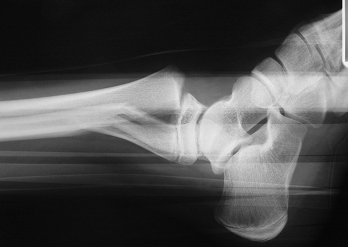

Fracture

décollement épiphysaire de type II de type marginale

postérieure. |